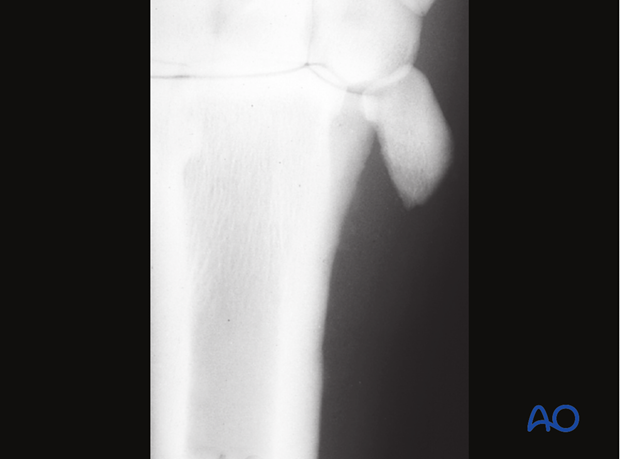

Example of a postoperative complication with fixation failure.

In this case, screws were also inserted into the third metacarpal/-tarsal bone. Screws without a plate are too fractious to achieve stable fixation of the splint bone to the third metacarpal/-tarsal bone.